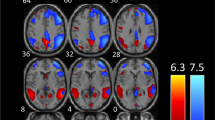

When comparing patient groups among them and with HC, during moderately painful THS (51°), we observed: i) a significantly greater BOLD-response in left lingual gyrus, inferior parietal lobe, inferior frontal gyrus (see Figs. 1 and 2) and cerebellum in patients with MwA compared to MwoA patients (Fig. 3); ii) a significantly greater BOLD-response in the cerebellum in patients with MwA compared to HC (Fig. 3); iii) a significantly greater BOLD-response in medial frontal gyrus (see Figs. 1 and 2) in patients with MwA compared to HC; iv) no other difference in BOLD response has been observed between both MwA patients group and MwoA patients group and HC.

Talairach coordinates of significant cluster differences between groups are reported in Table 2. Mean values of percentage BOLD signal changes were extracted from following clusters: lingual gyrus (MwA: 0.12 ± 0.03; HC: 0.031 ± 0.02; MwoA: − 0.029 ± 0.02; MwA vs HC p:0.005, MwA vs MwoA p < 0.001, MwoA vs HC p:0.02), inferior parietal lobule (MwA: 0.11 ± 0.02; HC: 0.05 ± 0.03; MwoA: − 0.03 ± 0.05; MwA vs HC p:0.06, MwA vs MwoA p < 0.001, MwoA vs HC p:0.002), inferior frontal gyrus (MwA: 0.13 ± 0.03; HC: 0.06 ± 0.03; MwoA:-0.05 ± 0.02; MwA vs HC p:0.13, MwA vs MwoA p < 0.001, MwoA vs HC p:0.001), medial frontal gyrus (MwA: 0.13 ± 0.03; HC: 0.01 ± 0.02; MwoA:0.04 ± 0.02; MwA vs HC p: p < 0.001, MwA vs MwoA p:0.008, MwoA vs HC p:0.39) and cerebellum (MwA: 0.11 ± 0.02; HC: 0.03 ± 0.01; MwoA: − 0.02 ± 0.01; MwA vs HC p < 0.001, MwA vs MwoA p < 0.001, MwoA vs HC p:0.006) (see Figs. 2, 3 and 4).

Correspondence of function and structure of midline and lower structures of the cerebellum showing interictal increased response to THS in MwA patients. The coloured areas highlight the uvula, the tonsils and the biventer lobule. (adapted from Duvernoy HM, 1995). THS: trigeminal heat stimulation; MwA = migraine with aura.

Beside the activation of AVN, we observed a significantly increased BOLD-response to THS in the midline and lower structures of the cerebellum (e.g.: uvula, tonsils and biventer lobule) in patients with MwA when compared with both patients with MwoA and HC. Although its role has been previously underestimated in human pain perception, it is now well-known that cerebellum is involved in pain processing [26, 27] as demonstrated also by altered experimental pain perception after cerebellar infarction [28]. More specifically, during trigeminal nociception, the activation of specific cerebellar areas as well as their functional connections with both the descending anti-nociceptive network and cortical hubs of pain processing have been observed [29].

Based on these observations, several structural and functional studies have been conducted in the attempt to clarify the putative role played by the cerebellum in migraine [30]. Among these, an increased activity of the cerebellar crus with a concomitant decreased functional connectivity with thalamus have been demonstrated during trigeminal stimulations. The findings suggest a recruitment of cerebellar additional resources to overcome the diminished functional cerebellar-thalamic connectivity in patients with MwoA [30]. However, the cerebellar compensatory mechanism seems to be ineffective, inducing a dysfunctional thalamic gating of external stimuli addressed to cortical areas and leading to susceptibility for migraine attacks [31]. Interestingly, a reduced cerebellar inhibitory control on cerebral cortex has been supported also in patients with MwA, using a transcranial magnetic stimulation protocol [32].

The increased cerebellar activity founded in the present study suggest the same compensatory and ineffective, in other word “maladaptive”, mechanism in patients with MwA during trigeminal nociceptive experience.

Considering our cortical and cerebellar findings, based on the well-known connections between cerebellar structures (e.g. pyramid, uvula, tonsils and biventer lobule) and AVN [33, 34] we speculate that the AVN hyperresponsiveness to THS might be due to the lack of cerebellar inhibitory control on thalamic sensory gating and, thus, on the brain cortex.